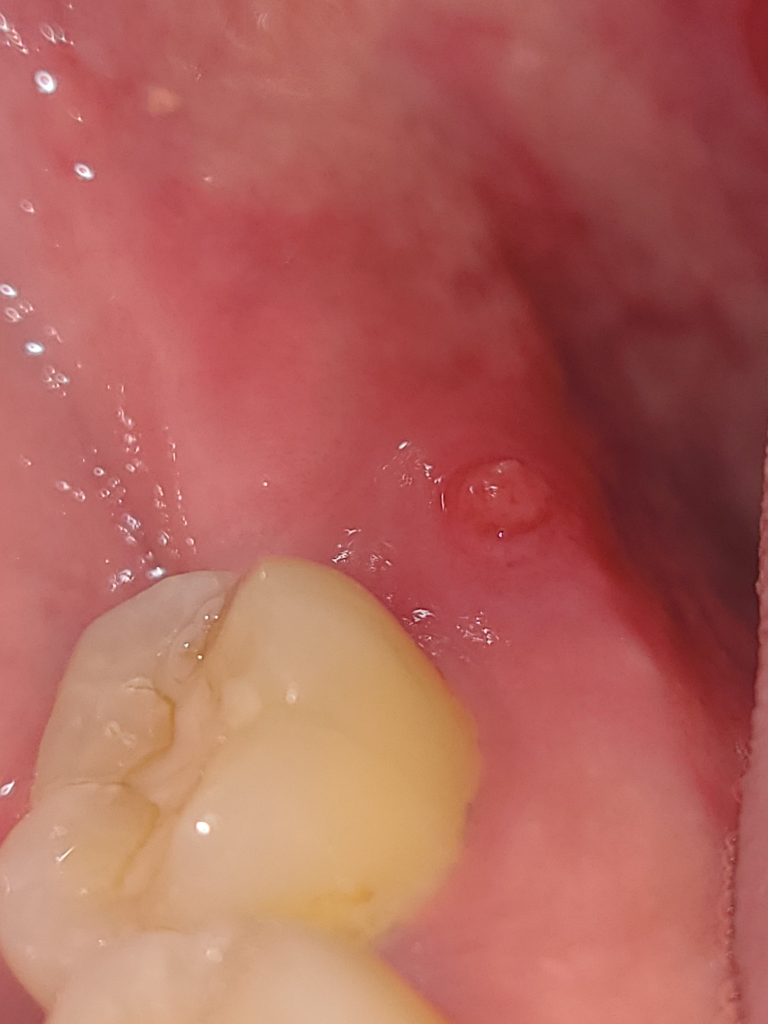

단순 잇몸 염증이라면 치과에 가셔서 마취후에 제거하시면되지만, 뿌리끝에서 나오는 염증이라면 신경치료를 하셔야될수도 있습니다.

안녕하세요. 최석민 치과의사입니다.

사진상으론 점액유출현상 또는 점액류(mucocele)가 의심됩니다. 주로 작은 타액선 배설관에 가해진 외상에 의해 발생하게 됩니다. 치료는 병소의 외과적인 절제입니다. 구강내과가 진료과로 있는 치과에 가서 정확한 진단을 받아보시기 바랍니다. 상기 말씀드린 내용은 사진만 보고 내린 잠정진단이며 정확하지 않을 수도 있습니다.